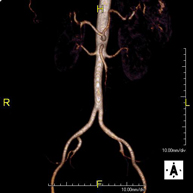

Prueba diagnóstica no invasiva que consiste en la obtención de imágenes de alta definición anatómica de todo el cuerpo mediante el empleo de un campo electromagnético y ondas de radio (con un emisor y un receptor). No utiliza radiación ionizante. Es una prueba muy importante en la búsqueda de metástasis en pacientes con neoplasia conocida. No requiere preparación previa. No es necesario el empleo de contraste paramagnético (Gadolinio). - Angio-RM Aorta abdominal

Prueba diagnóstica no invasiva que consiste en el estudio de la arteria aorta abdominal, obteniendo imágenes de alta definición anatómica mediante el empleo de un campo electromagnético y ondas de radio (con un emisor y un receptor). Es indispensable el uso de contraste paramagnético (Gadolinio). Sin embargo, no utiliza radiación ionizante. La calidad de las imágenes permite realizar reconstrucciones en 2D y 3D. Está indicado en aquellos pacientes con enfermedad vascular (aterosclerosis), estudio de aneurismas, en estudios pre-quirúrgicos de lesiones adyacentes a la aorta abdominal como "mapa" vascular, etc. - Angio RM Aorta-ilíaca

Prueba diagnóstica no invasiva que consiste en el estudio de la arteria aorta abdominal de las arterias ilíacas, obteniendo imágenes de alta definición anatómica mediante el empleo de un campo electromagnético y ondas de radio (con un emisor y un receptor). Es indispensable el uso de contraste paramagnético (Gadolinio). Sin embargo, no utiliza radiación ionizante. La calidad de las imágenes permite realizar reconstrucciones en 2D y 3D. Esta prueba está especialmente indicada como estudio pre-quirúrgico (mapa vascular) antes de intervenciones percutáneas o quirúrgicas de aorta abdominal y arterias ilíacas, estudio complementario en pacientes con isquemia de miembros inferiores, etc. - Angio RM Arterial extremidades inferiores

Prueba diagnóstica no invasiva que consiste en el estudio de la arteria aorta abdominal, obteniendo imágenes de alta definición anatómica mediante el empleo de un campo electromagnético y ondas de radio (con un emisor y un receptor). Es indispensable el uso de contraste intravenoso paramagnético (gadolinio). Sin embargo, no utiliza radiación ionizante. La calidad de las imágenes permite realizar reconstrucciones en 2D y 3D. Está indicado en aquellos pacientes con enfermedad vascular (aterosclerosis), estudio de aneurismas, en estudios pre-quirúrgicos de lesiones adyacentes a la aorta abdominal como "mapa" vascular… - Angio-RM Aorta iliaca

Prueba diagnóstica no invasiva que consiste en el estudio de la arteria aorta abdominal, obteniendo imágenes de alta definición anatómica mediante el empleo de un campo electromagnético y ondas de radio (con un emisor y un receptor). Es indispensable el uso de contraste intravenoso paramagnético (gadolinio). Sin embargo, no utiliza radiación ionizante. La calidad de las imágenes permite realizar reconstrucciones en 2D y 3D. Esta prueba está especialmente indicada como estudio pre-quirúrgico (mapa vascular) antes de intervenciones percutáneas o quirúrgicas de aorta abdominal, estudio complementario en pacientes con isquemia de miembros inferiores… - Angio-RM Arterias renales